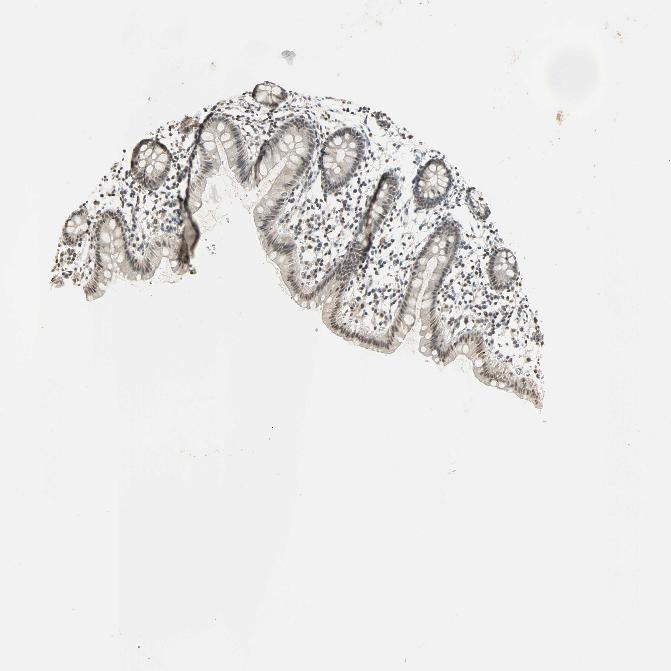

COLON - Antibody stainingi

Antibody staining in the annotated cell types in the current human tissue is reported as not detected, low, medium, or high, based on conventional immunohistochemistry profiling in selected tissues. This score is based on the combination of the staining intensity and fraction of stained cells.

Each image is clickable and will lead to virtual microscopy that enables deeper exploration of all samples and also displays staining intensity scores, fraction scores and subcellular localization as well as patient and tissue information for each sample.

Antibody HPA008751Antibody CAB005227

Endothelial cells MediumLow

Glandular cells HighLow

Peripheral nerve/ganglion Medium-